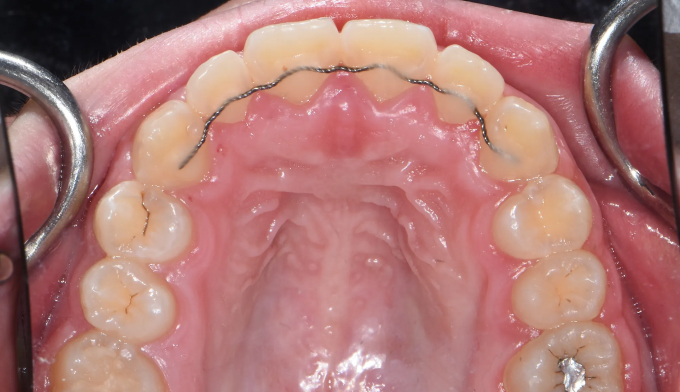

Before

앞니가 돌출되어있고, 특히 전반적으로 양치질이 부족하여 잇몸이 모두 부어있는 상태입니다.

치아들의 배열이 고르지 못한 상태에서는 양치질이 더욱 어려워지므로 구강위생상태에 더 신경을 써야 합니다.